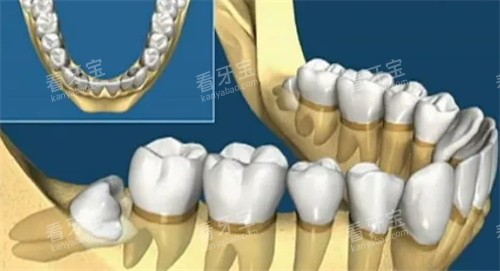

医生推了推眼镜:"这个要看具体情况。如果是普通牙齿,我们一般会建议先尝试修补。但智齿比较特殊,位置靠后很难清洁,即使补了也很容易再次蛀坏。"

医生看出了我的恐惧,耐心解释道:"补是可以补,但你要想清楚几点:头一,智齿补牙难度大,费用也高;第二,补完后你可能还是很难清洁到位;第三,如果补牙后再次蛀坏,到时候情况可能更严峻。"

"年轻人,你这颗智齿已经蛀到接近神经了,而且位置不正,清洁确实很困难。我的建议是拔除,虽然听起来可怕,但长远来看对你更好。"